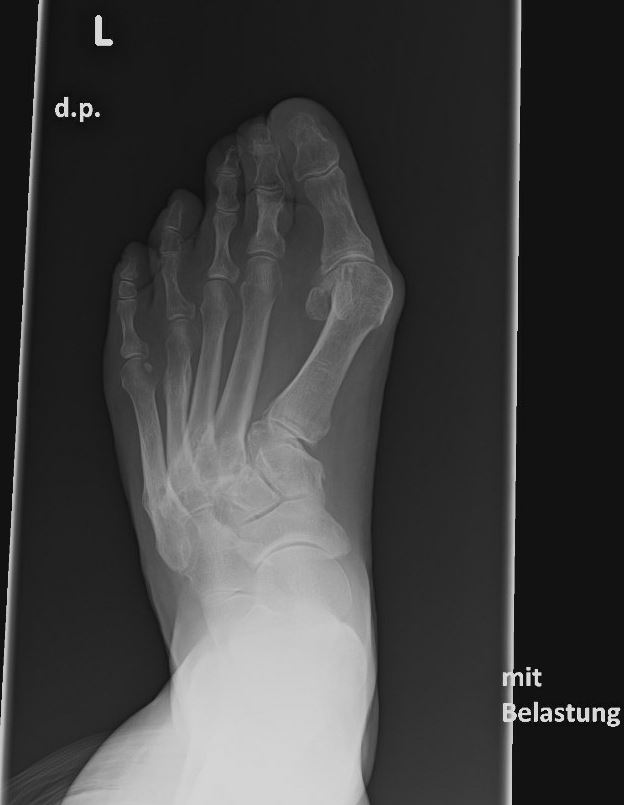

Eine Röntgenaufnahme unter Belastung mit Abbildungen des ganzen Fußes a. p. (mit 15-20° Röhrenkippung) und seitlich, sowie Schrägaufnahmen, reichen meist zur Diagnose. Manchmal ist ein MRT und DVT ergänzend hilfreich. Selten wird die Indikation für ein SPECT CT gestellt (Abb. 6).

Zum Lesen der Bildbeschreibung und zur Vollansicht bitte das Bild anklicken. Bild: C. Hase.

• konventionelle Röntgenbilder mit Belastung im Stehen a. p. und seitlich, ggf. schräg (Abb. 9, 10 und 11).